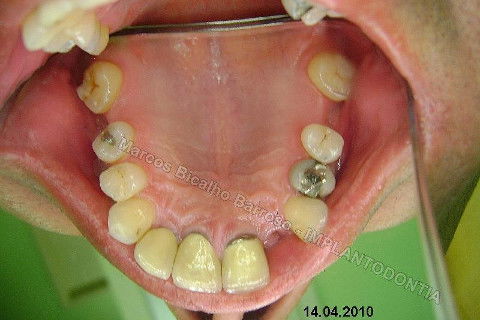

Este caso tem o objetivo de demonstração da técnica que normalmente sigo ; em casos onde ocorre fratura da raiz e consequentemente abscessos, com ou sem formação de fístula. Neste caso fiz a exodontia com preenchimento do alvéolo com biomaterial (osso bovino liofilizado + coágulo do paciente). Após 90 dias, mais ou menos, instalei o implante. Esperei mais 4 meses e realizei ontem (12/11/2010) a instalação do cicatrizador com o cuidado de preservar tecido mole, sem remoção de material, apenas afastando gengiva e "enrolando" a sobra de mucosa em direção a face vestibular, para promover conservação de papila futuramente. Se ocorrer excesso de papila, sem problema, remove-se um pouco, mas a intenção é não deixar faltar, o que resultaria em indicação para enxertos gengivais.

Fotos do caso